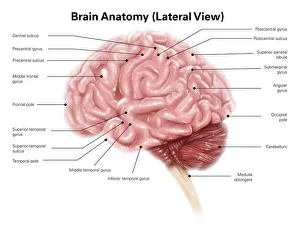

The central nervous system, the intricate network that governs our every thought and movement, is a marvel of complexity. From the delicate cerebellum tissue to the detailed light micrograph capturing its essence, we are reminded of its importance in maintaining balance and coordination. Anatomy comes alive as we explore the human brain from an inferior view. The intricacy of brain fibers is revealed through DTI MRI scans like C017/7099 and C017/7035, showcasing their vital role in transmitting information throughout this extraordinary organ. Artistic renderings bring us closer to understanding the medulla oblongata's significance within the brain. Its portrayal in various artworks allows us to appreciate how it controls essential functions such as breathing and heart rate. As we delve deeper into studying the central nervous system, models of the human brain provide invaluable insights into its structure and organization. Lateral views reveal countless regions responsible for cognition, emotion regulation, sensory perception, and motor control. Microscope slides offer glimpses into nerve cells' intricate architecture—a testament to their ability to transmit electrical signals at lightning speed. Meanwhile, glial stem cell cultures captured under a light microscope remind us of their crucial role in supporting neuronal function. Finally, artistic representations unveil the limbic system's enigmatic nature—an interconnected web responsible for emotions and memory formation. These captivating artworks allow us to visualize this complex network within our brains. Exploring these hints provides a glimpse into the awe-inspiring world of our central nervous system—the very foundation upon which our thoughts, actions, memories reside—reminding us just how remarkable our brains truly are.